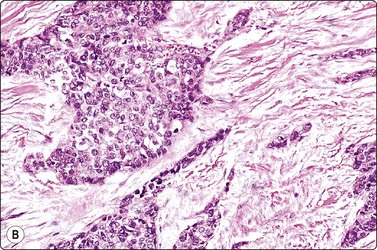

image image

Fig. 11.11 Adenocarcinoma (pancreas) moderately differentiated

(A) Sheets showing disorganization and nuclear pleomorphism; background of necrotic debris (H&E, IP); (B) Disorganized clusters with some acinar arrangements (MGG, HP).

Criteria for diagnosis33,70-73

Disordered monolayer sheets, microglandular patterns, nuclear crowding; loss of cell cohesion,

Nuclear criteria of malignancy with contour irregularity and fairly distinctive margination of chromatin,

Moderate amount of cytoplasm, often mucin vacuoles, indistinct cell borders,

Evidence of necrosis, mitoses, macronucleoli and hyperchromasia in poorly differentiated forms.

Almost all adenocarcinomas arising in the pancreas are of ductal origin, without unique features permitting absolute distinction from carcinomas arising in the biliary tree. The characteristic FNB pattern is of crowded ‘drunken’ monolayered sheets, with moderately tall columnar palisading cells at luminal edges. Smaller aggregates commonly show rounded glandular structures with feathered edges, or three-dimensionality. Cytoplasmic borders may be very well demarcated in better-differentiated forms; in other cases, the monolayer sheets appear syncytial. The diagnosis of malignancy ultimately depends on nuclear features, which range from very subtle alterations to overly malignant criteria with decreasing differentiation (Figs 11.9-11.11). In an assessment of individual criteria by regression analysis, Cohen and colleagues extracted as most important: anisocytosis (4 : 1), nuclear enlargement and molding, with combined sensitivity of 98% using all three criteria to distinguish malignant from benign.70 In a similar study, Robins, Katz and Evans ascribed major status to nuclear crowding, contour and chromatin irregularity, minor status to single cells, mitoses and enlarged nuclei,33 requiring two major, or one major and two minor criteria for the definitive diagnosis of malignancy. Focusing specifically on the most challenging area, the recognition of well-differentiated carcinoma, Lin and Staerkel listed the following features: nuclear enlargement > 2 rbc (99%), anisonucleosis 4 : 1 (97%), nuclear membrane irregularity (97%), and crowding/overlapping/three-dimensionality (92%).73